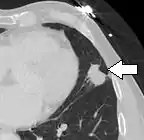

- Pleural retraction is far more common in cancers.[9] It is the pulling of visceral pleura towards the nodule.[9]

Nodule with pleural retraction.[9]

In this case, pleural retraction is seen as a triangular fat component.[9]